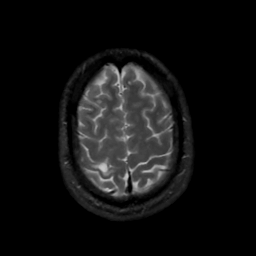

MR Study #8, March 31, 1991 -- Slice #42